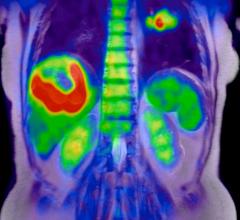

July 16, 2020 — Whole body positron emission tomography (PET) has, for the first time, illustrated the existence of ...

July 16, 2020 — Results from the first study using uEXPLORER to conduct total-body dynamic positron emission tomography ...

July 14, 2020 — For the first time, physicians can examine the systemic burden of inflammatory arthritis simultaneously ...

April 10, 2020 — Combining 89Zr-labeled antibodies with total-body positron emission tomography (PET) has extended the ...